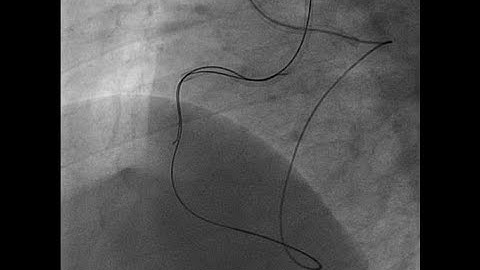

Right coronary artery CTO treated with retrograde reverse CART and rotational atherectomy